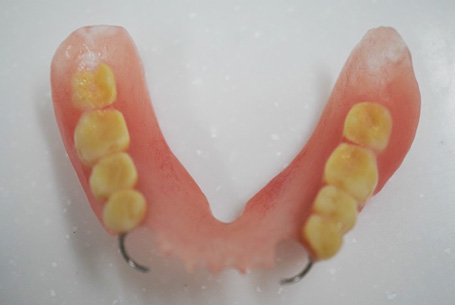

完成した下の入れ歯

模型を咬合器に装着し、バネの製作・人工歯排列をしました。バネは見えにくいように、歯頸部よりに製作しました。急ぎであったため、試適は行わず、埋没・填入・割り出しし、入れ歯を完成させました。